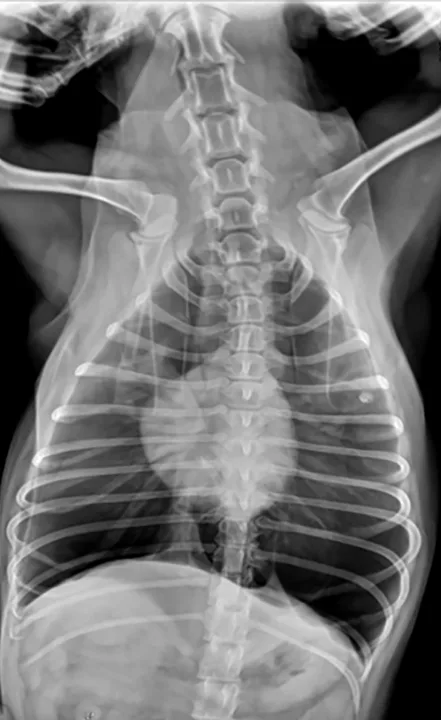

Veterinary nurses taking thoracic radiographs must remember that radiation safety comes first. Appropriate personal protective equipment should be used. Hands in the primary beam are unacceptable and dangerous. (See Figures 1 & 2.)

Figure 1 Ventrodorsal view obtained while holding the patient’s thoracic limbs with the hands

Images courtesy of Janet Paquette, AS, LVMT